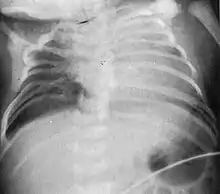

| Radiograph depicting typical skeletal features of Jarcho-Levin syndrome, subtype spondylothoracic dysplasia. Note fanlike configuration of the ribs, with extensive posterior fusion, along with multiple vertebral segmentation defects. | |

Spondylothoracic dysplasia, or STD, has been repeatedly described as an autosomal recessively inherited condition that results in a characteristic fan-like configuration of the ribs with minimal intrinsic rib anomalies. Infants born with this condition typically died early in life due to recurrent respiratory infections and pneumonia due to their restricted thorax.[3][4][5] Recently, a report[6] has documented that actual mortality associated with STD is only about 50%, with many survivors leading healthy, independent lives.

In contrast to STD, the subtype spondylocostal dysostosis, or SCD features intrinsic rib anomalies, in addition to vertebral anomalies. Intrinsic rib anomalies include defects such as bifurcation, broadening and fusion that are not directly related to the vertebral anomalies (such as in STD, where extensive posterior rib fusion occurs due to segmentation defects and extreme shortening of the thoracic vertebral column).[6] In both subtypes, the pulmonary restriction may result in pulmonary hypertension, and have other potential cardiac implications.[7]